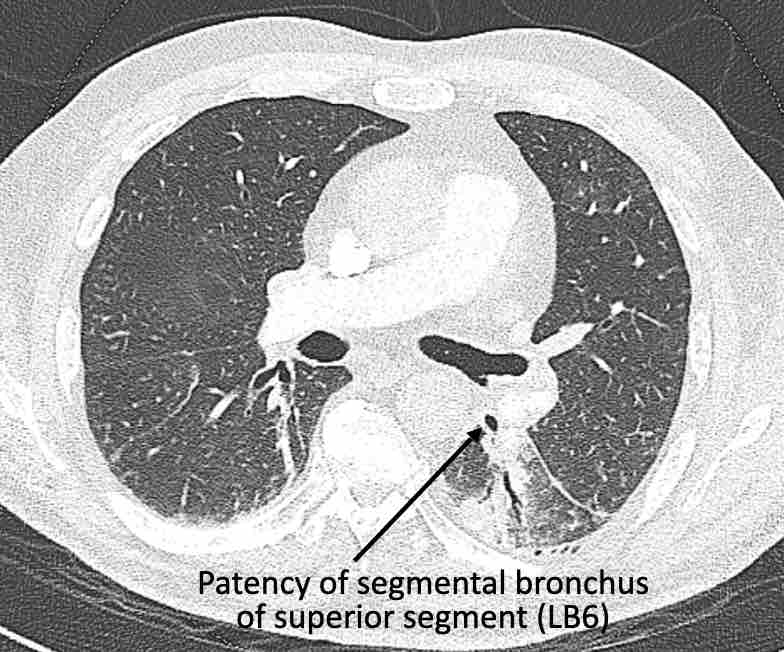

Hình ảnh

Cuộn qua các hình ảnh.

Theo dõi các phế quản của thùy dưới phổi trái cho thấy nhánh phân thùy đầu tiên của thùy dưới phổi trái còn thông; đó là phế quản phân thùy đỉnh.

Các ghim phẫu thuật nằm tại vị trí của các phân thùy đáy sau và đáy bên (LB9/10), vốn thường được cắt bỏ cùng nhau.

Do đó, phân thùy phổi có hình ảnh kính mờ và đông đặc phải là phân thùy đáy trước của thùy dưới phổi trái (LB8).

Động mạch phổi đến phân thùy này cũng không ngấm thuốc cản quang, và bản đồ tưới máu iốt nhấn mạnh thêm tình trạng nhồi máu.

Bệnh nhân đã được phẫu thuật lại và tiến hành cắt bỏ phân thùy bị nhồi máu, với xác nhận qua giải phẫu bệnh.